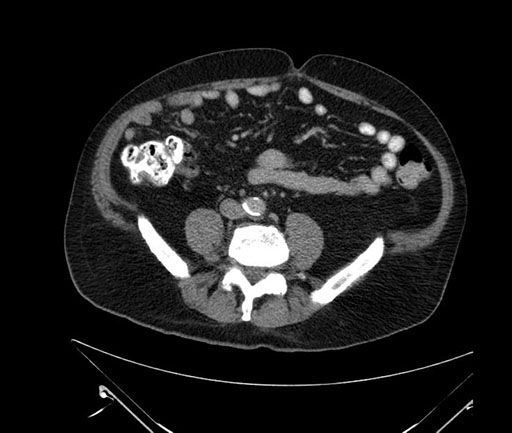

Axial - stented